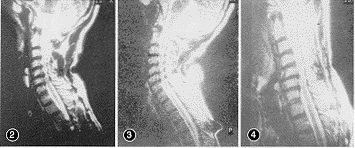

中立位时,膨出或突出的颈椎间盘C3~4、C4~5、C5~6、C6~7从前方压迫硬膜囊、脊髓(图2,插Ⅱ)。过伸位时,硬膜囊、脊髓被压呈串珠状,前方有突出加重的椎间盘,后方为内陷折叠的黄韧带(图3,插Ⅱ)。过屈位时,突出椎间盘仅C5~6压迫硬膜囊及脊髓较明显,其余间隙椎间盘部分还纳(图4,插Ⅱ)。测量结果见表1~7。椎管/椎体中矢径之比小于0.75定为椎管狭窄〔1〕,本组31例中有14例,占45.2%。通过测量,各间隙隙椎间盘突出大小在屈伸动态变化中有显著性差异(P<0.01),而硬膜囊前间隙变化均无显著性差异(P>0.05)。

图2 中立位:C3~4、C4~5、C5~6、C6~7膨出或突出的椎间盘从前方压迫硬膜囊,C4~5、C5~6、C6~7后方黄韧带折叠内陷图3 过伸位:前方膨出或突出加重,C3~4、C4~5、C5~6、C6~7后方的黄韧带折叠内陷亦加重,硬膜囊、脊髓呈串珠状 图4 过屈位:仅C5~6压迫硬膜囊明显,C3~4、C4~5、C6~7椎间盘部分还纳,内陷折叠的黄韧带消失

3.4 颈椎后伸时,后纵韧带和椎间盘后部纤维环高度减低,椎间盘膨出增大,黄韧带突入椎管内(图3)。脊髓受前后力量的挤压,受压节段明显变细,甚至呈串珠状改变。颈椎屈曲时(图4),黄韧带内陷消失,脊髓的后方压迫缓解。后纵韧带牵张,椎间盘膨隆可还纳,而突出的C5~6依然明显压迫硬膜囊、脊髓,椎管截面积增大,脊髓被拉长、变细。与中立位及过伸位比较有显著性差异(P<0.05)。屈曲时,脊髓牵拉向头端移动,齿状韧带和神经根的限定作用加强。脊髓、脊膜已承受相对较大的生理性张力。加之未完全回纳的椎间盘使脊髓受压,截面积更加缩小,拉伸载荷与截面积成反比,必然使脊髓面承受的拉应力增大,使承受压力的对侧脊髓承受更大的弯曲拉应力,加重脊髓缺血。